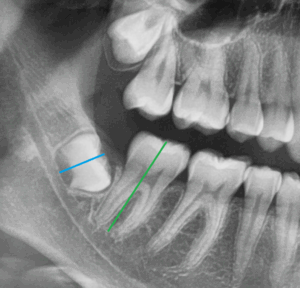

Weisheitszahn kann Zähne verschieben – Auf dem ersten Röntgenbild ist ein Weisheitszahn (schwarzer Pfeil) abgebildet, dessen Wurzelwachstum noch nicht abgeschlossen ist. Lediglich die Zahnkrone dieses Zahnes ist ausgebildet. Auf der nächsten Abbildung ist die Zahnachse des gleichen Weisheitszahnes (blaue Linie) und des Nachbarzahnes (grüne Linie) dargestellt. Im Rahmen des Wurzelwachstums kann der Weisheitszahn die davorliegenden Zähne verschieben. Besteht die Gefahr, dass der kieferorthopädische Behandlungserfolg in Gefahr ist, dann sollten solche Weisheitszähne entfernt werden.